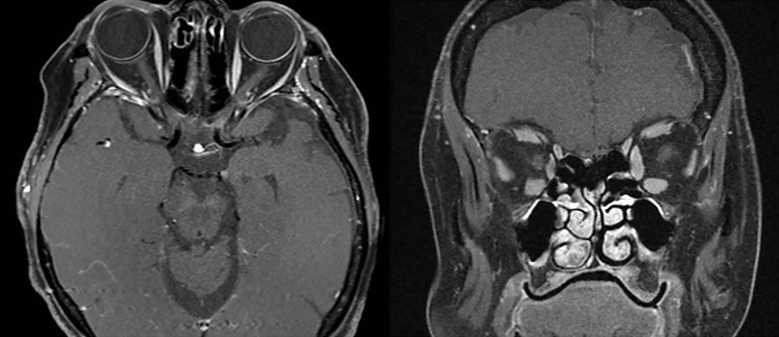

Case presentation: We herein present a case of a 67-year-old woman presenting with sudden decrease in vision in the right eye. The patient underwent a 3T MRI of the orbits and brain 5 days post vision loss which returned normal right optic nerve appearance at presentation (no edema, enhancement or increased T2 signal). Further serological testing of the MOG antibody returned positive (1:100) while APQ4 antibodies were negative. This yielded a diagnosis of MOG-IgG-ON. Subsequently, the patient was treated with IV methylprednisolone 1 g daily for 5 days followed by prednisone 1 mg/kg, resulting in marked improvement in vision.